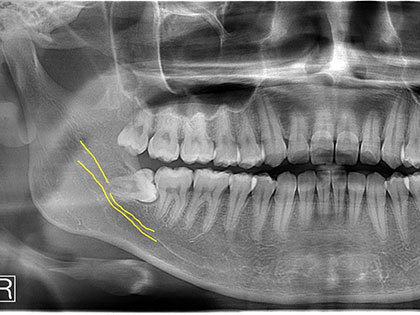

親知らず抜歯症例

親知らず抜歯症例6

左右下親知らずを抜歯したいとの事で来院、治療を希望された患者様の症例になります